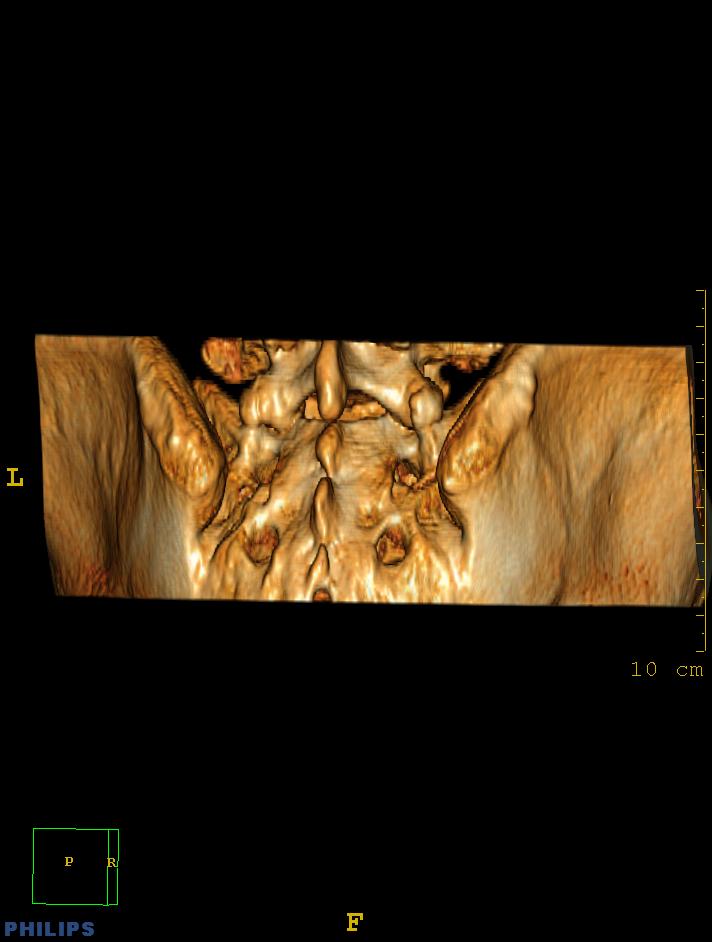

标题: CT14032:M34Y,双侧骶髂关节 [打印本页]

标题: CT14032:M34Y,双侧骶髂关节

m,34岁,腰痛三年,腰椎活动度明显减低,x片示腰椎竹节样改变

双侧骶髂关节骨性融合,软骨下囊性变,结合脊柱竹节样改变,典型的强直性脊柱炎。